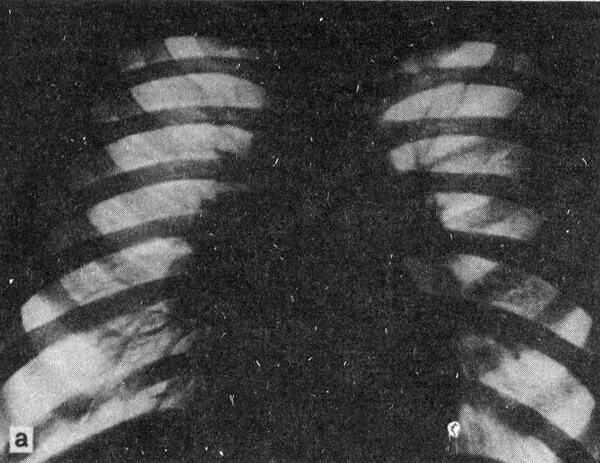

Увеличение внутригрудных лимфатических узлов